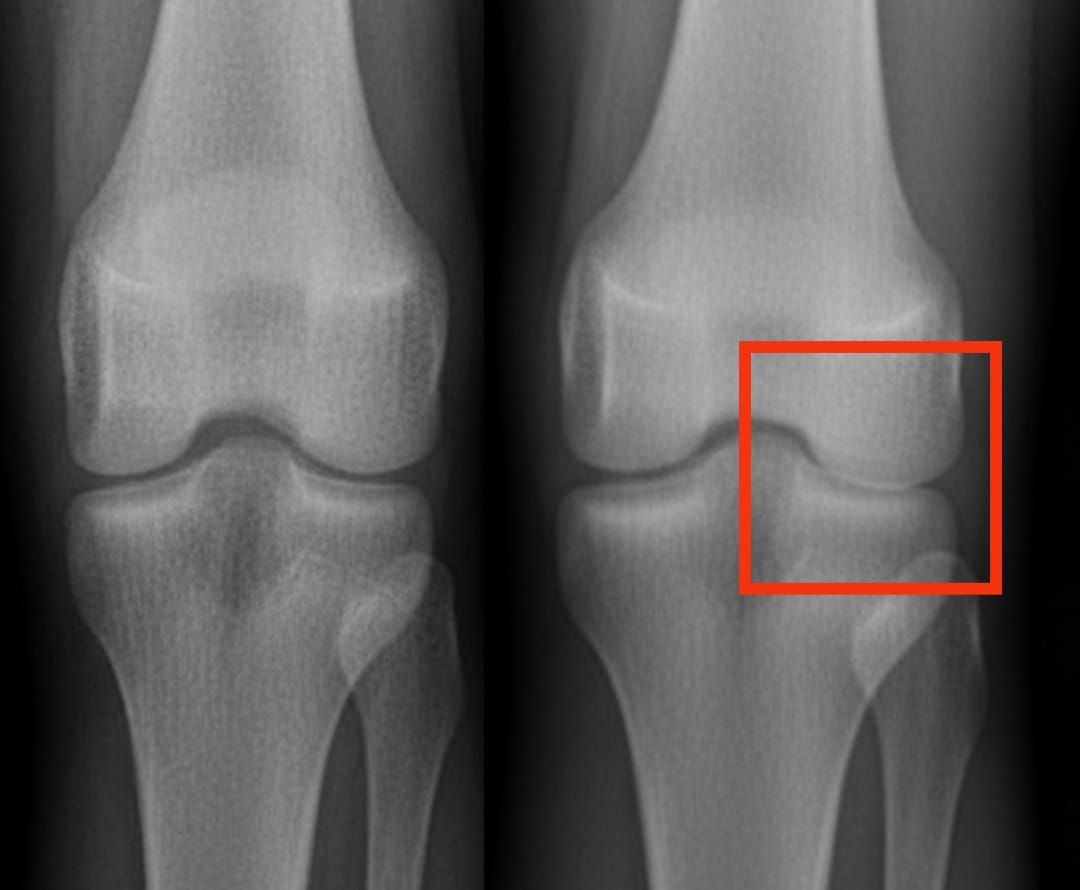

L’arthrose du genou touche des centaines de millions de personnes dans le monde. Elle se caractérise par une usure progressive du cartilage, entraînant douleurs et difficultés à bouger. Parmi les solutions proposées, les injections de plasma riche en plaquettes suscitent un intérêt croissant. Ce traitement utilise le propre sang du patient, concentré en plaquettes, pour stimuler la réparation des tissus et réduire l’inflammation.

Une analyse récente a comparé l’efficacité du plasma riche en plaquettes à celle d’autres injections courantes : l’acide hyaluronique, les corticoïdes et un placebo salin. Les résultats montrent que le plasma riche en plaquettes améliore significativement la douleur et la mobilité après six mois, avec des bénéfices qui persistent jusqu’à un an. Ces améliorations sont plus marquées que celles obtenues avec l’acide hyaluronique ou les corticoïdes, et bien supérieures à celles du placebo.